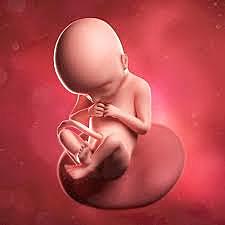

• Semana 8

22

Semana 8

los párpados están más desarrollados

las características externas del oído comienzan a tomar su forma final.

continúa el desarrollo de las características faciales

los intestinos rotan